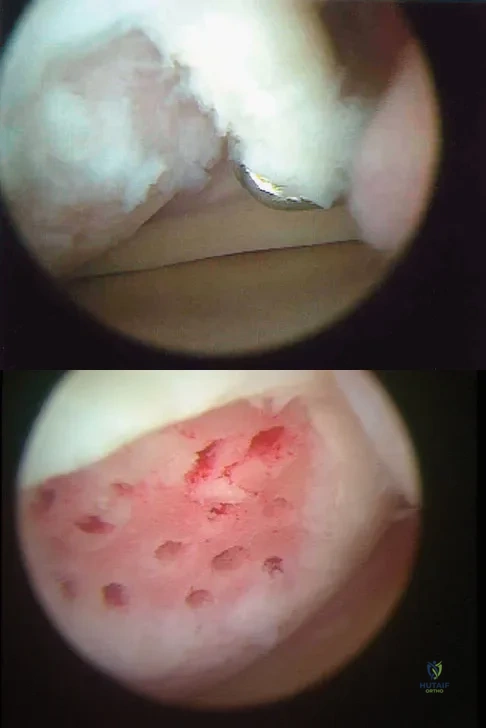

A 13-year-old girl who competes in gymnastics reports the insidious onset of lateral left elbow pain over the past 6 months. She also notes occasional catching episodes in the elbow; however, she denies any history of trauma. Examination reveals tenderness over the lateral epicondyle and extensor muscle origin. The elbow is stable and has full flexion, but lacks 10 degrees of full extension. An AP plain radiograph and an MRI scan are shown in Figures 17a and 17b. Management of the elbow should consist of

Explanation

The radiograph and MRI scan show osteochondritis dissecans of the capitellum, and the patient's history suggests a loose body. The treatment of choice is arthroscopic removal of the loose body and microfracture of the crater. Excision of the radial head, a cortisone injection, or tennis elbow release does not treat the pathology in the capitellum. Nonsurgical treatment would not relieve the mechanical symptoms of the loose body or promote healing in the crater. Baumgarten TE, Andrews JR, Satterwhite YE: The arthroscopic classification and treatment of osteochondritis dissecans of the capitellum. Am J Sports Med 1998;26:520-530. Jackson DW, Silvino N, Reiman P: Osteochondritis in the female gymnast's elbow. Arthroscopy 1989;5:129-136.